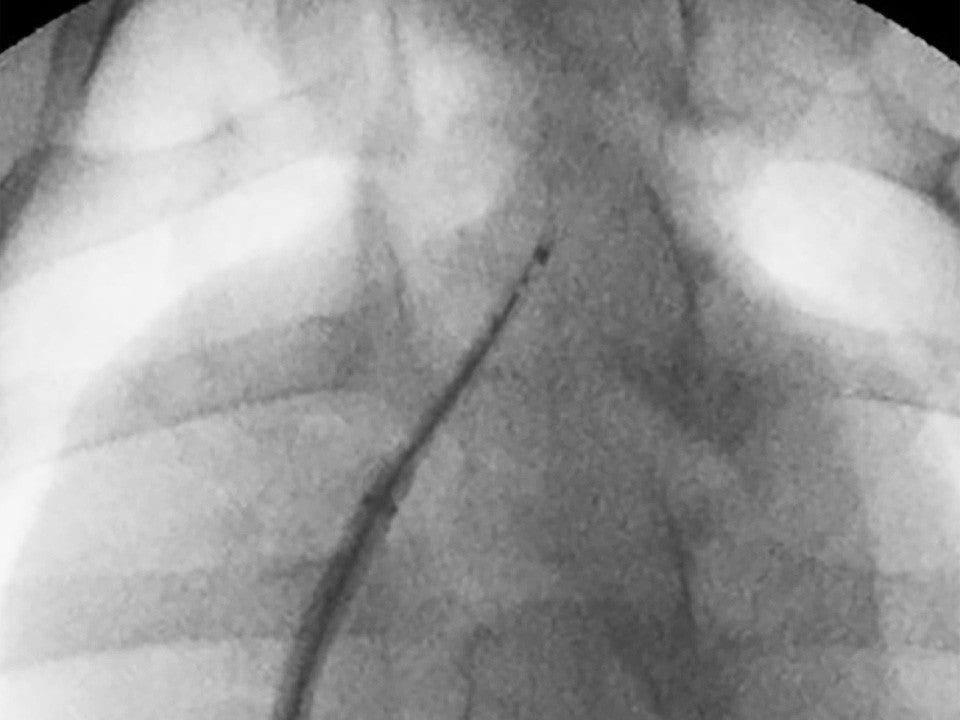

Image demonstrating that VersaCross Access Solution is radiopaque.

Radiopaque

Visualize your entire solution on fluoroscopy